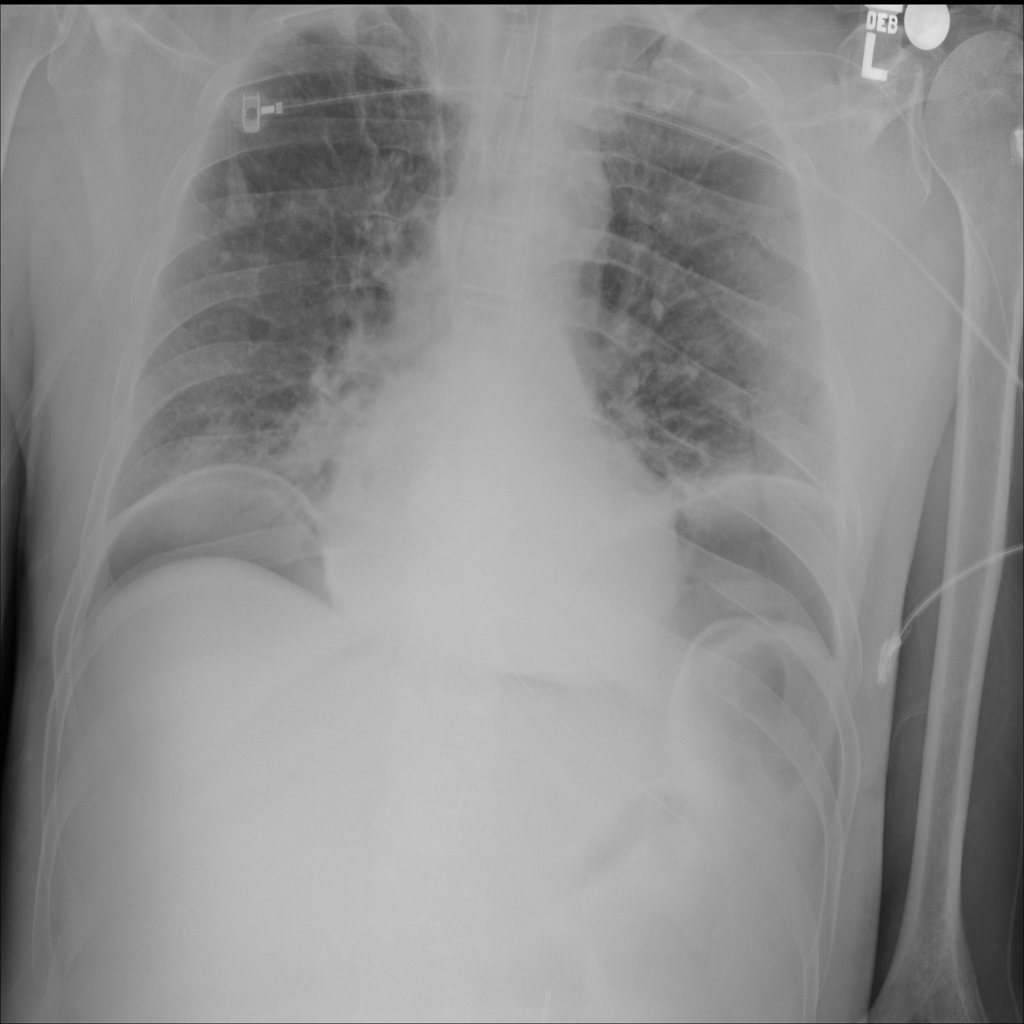

PAT-24D9 · IMG-006Edema

PAT-24D9 · IMG-006

AP